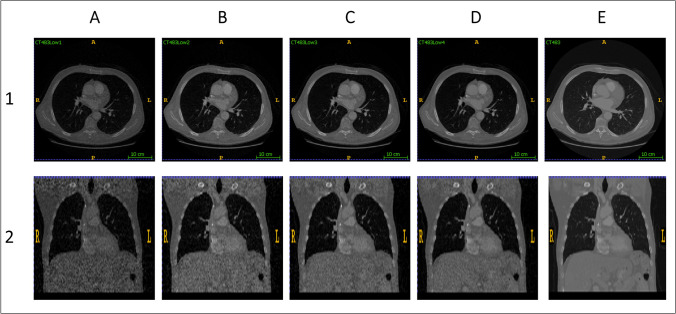

The aim of this study was to develop a deep learning method for analyzing CT images with varying doses and qualities, aiming to categorize lung lesions into nodules and non-nodules. This study utilized the lung nodule analysis 2016 challenge dataset. Different low-dose CT (LDCT) images, including 10%, 20%, 40%, and 60% levels, were generated from the full-dose CT (FDCT) images. Five different 3D convolutional networks were developed to classify lung nodules from LDCT and reference FDCT images. The models were evaluated using 400 nodule and 400 non-nodule samples. An ensemble model was also developed to achieve a generalizable model across different dose levels. The model achieved an accuracy of 97.0% for nodule classification on FDCT images. However, the model exhibited relatively poor performance (60% accuracy) on LDCT images, indicating that dedicated models should be developed for each low-dose level. Dedicated models for handling LDCT led to dramatic increases in the accuracy of nodule classification. The dedicated low-dose models achieved a nodule classification accuracy of 90.0%, 91.1%, 92.7%, and 93.8% for 10%, 20%, 40%, and 60% of FDCT images, respectively. The accuracy of the deep learning models decreased gradually by almost 7% as LDCT images proceeded from 100 to 10%. However, the ensemble model led to an accuracy of 95.0% when tested on a combination of various dose levels. We presented an ensemble 3D CNN classifier for lesion classification, utilizing both LDCT and FDCT images. This model is able to analyze a combination of CT images with different dose levels and image qualities.